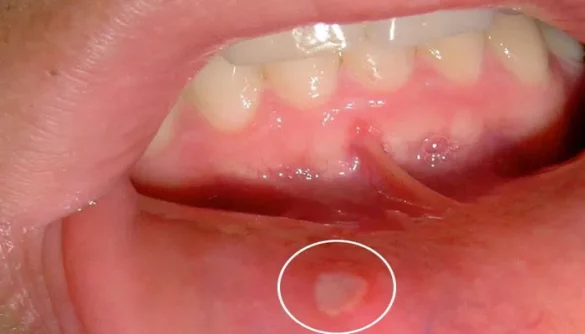

Denture sores, also known as denture-induced ulcers or irritations, occur due to various factors related to denture wear. The most common causes include poorly fitting dentures, excessive biting force, jaw clenching, and oral infections such as Candida (thrush) or gum disease. These sores can range from minor irritations to more severe ulcers, depending on their cause and severity.

When dentures do not fit properly, they can cause pressure spots on the gums, leading to soreness. Additionally, if dentures slide around in the mouth, they can repeatedly strike certain areas, causing abrasion and irritation. The healing process for these sores can vary significantly based on their severity and the effectiveness of the care provided.

Severity of the Sores: Minor sores typically heal within a few days to a week with proper care, while more severe sores or those caused by infections may take longer, often between one to two weeks.